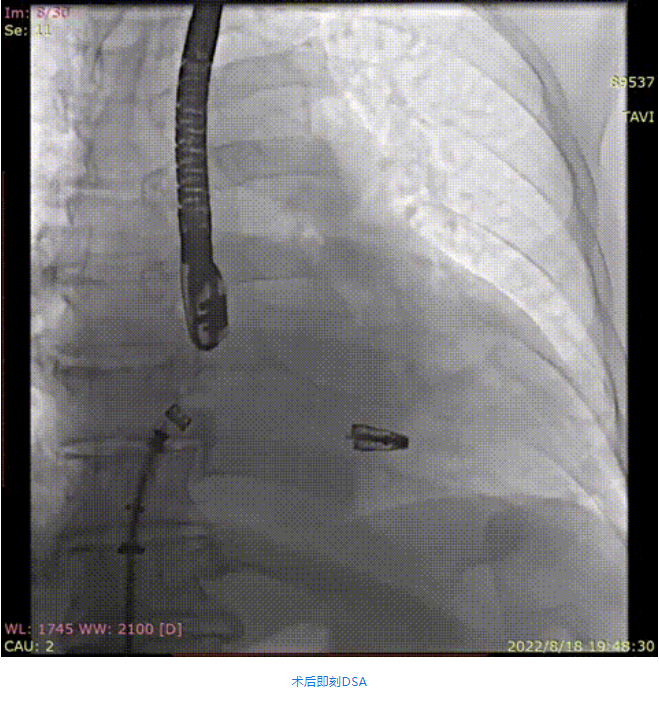

手術采用全身麻醉插管,經(jīng)股靜脈-房間隔入路,在TEE和DSA引導下完成房間隔穿刺。置入瓣膜夾系統(tǒng)后,在左房調(diào)整瓣膜夾的位置和軸向,后進入左室,在TEE引導下捕捉二尖瓣前后瓣葉,并關閉瓣膜夾。經(jīng)TEE反復確認手術效果后最終鎖定并釋放瓣膜夾。術后即刻超聲顯示瓣膜夾位置穩(wěn)定,功能良好,肺靜脈逆流和左房壓都明顯好轉。